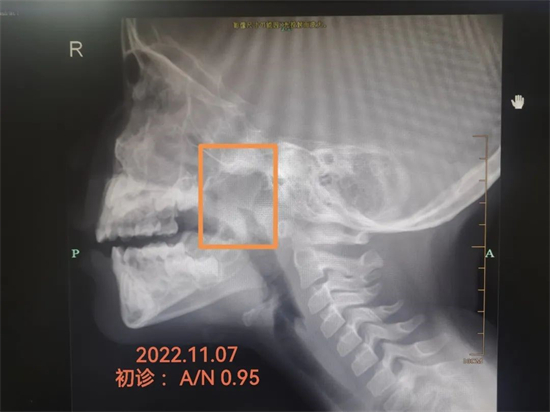

经鼻咽部侧位片检查后证实洛洛的腺样体的确有肿大,而且是重度,堵塞95%,达到了手术的指征。

经过4周的治疗,洛洛复查鼻咽部侧位片显示明显缩小,只是轻度肥大,不需要做手术了。